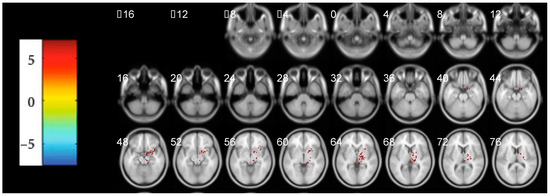

3.3. The Abnormal Activated Brain Regions by mfALFF Analysis

| Region Label | Cluster/Voxels | Peak t-Value | Montreal Neurological Institute (MNI) Coordinates | |||

|---|---|---|---|---|---|---|

| x | y | z | ||||

| Positive | Thalamus | 158 | 9.730 | 6 | −21 | 9 |

| Inferior Parietal Lobule | 220 | 10.612 | −45 | −27 | 24 | |

| Cingulate Gyrus | 110 | 7.665 | −6 | −15 | 45 | |

| Publisher’s Note: MDPI stays neutral with regard to jurisdictional claims in published maps and institutional affiliations. |